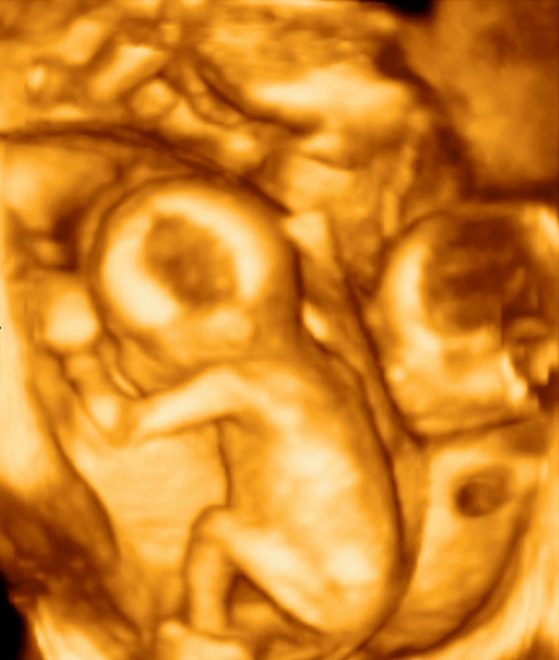

Zdravniki so pričakovali, da bo Halime rodila sedem otrok, saj so tako pokazali pregledi z ultrazvokom v Maliju in Maroku, zato sta dva dodatna dojenčka, deček in deklica, vse presenetila.